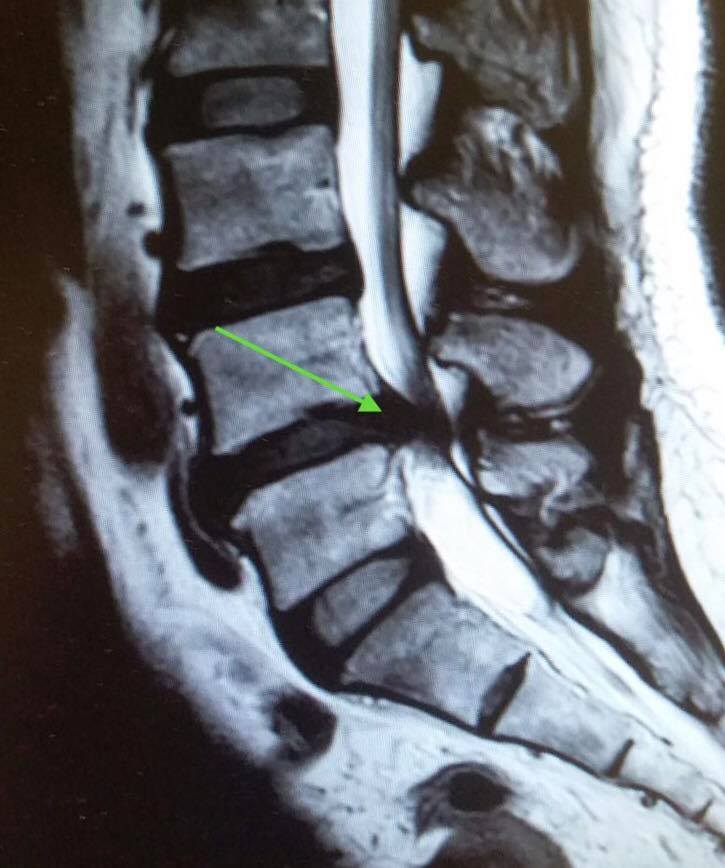

半急症類別,及早手術減壓...以防止神經永久受損而不能服原.

1. 引致椎間盤突出

2. 和因退化及腰椎不穏定…而增生肥大的韌帶

兩者一起擠壓著馬尾神經線.

現在只要是用2cm 的微創傷口…及顯微鏡下…兩小時的手術…便順利完成拯救所有馬尾神經線了….醒來後….妳能在丈夫及女兒面前即時表示….覺得雙腳非常有力…及所有痺痛症狀即時消失….所以請不要給非專業的嚇怕….會真正導致妳下身癱瘓及大小便失禁的計時炸彈已經拆除….無需要再有任何後顧之憂….亦可照原定計劃….下星期搭飛機去旅遊吧!